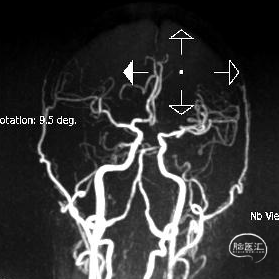

术后给予替罗非班静脉泵入,术后第二天进行MRA。